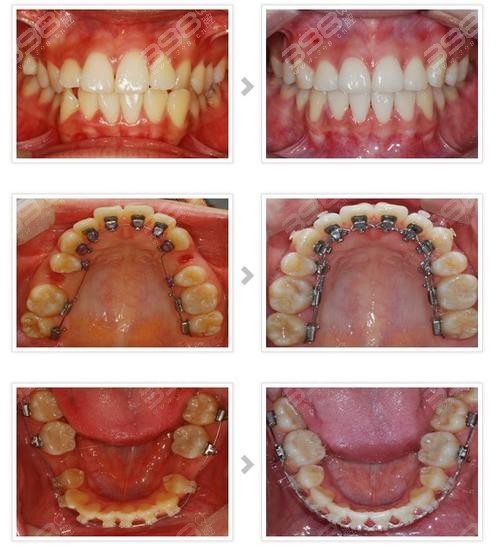

另一款隐形矫正器正在被牙友们所熟知,那就是eBrace舌侧隐形矫正,虽然能够做舌侧矫正的医生并不多,但是它的矫正结果确实让人感觉惊艳!不需要自律的摘戴牙套,在技术正畸医生手下,不齐的牙齿和不良的咬合关系就会得到改善!